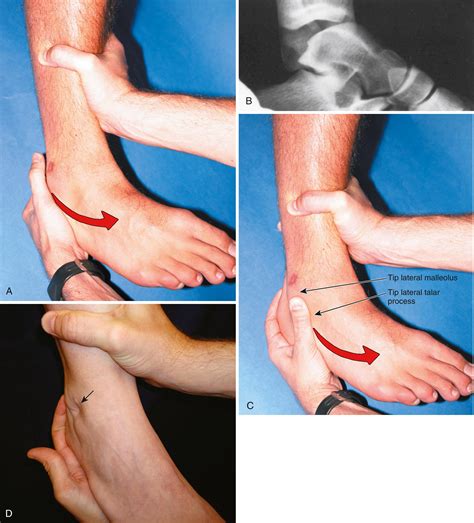

Performing the Anterior Drawer Sign Test

To perform the Anterior Drawer Sign test, follow these steps:

• Position the patient supine (lying on their back) with the knee flexed to approximately 90 degrees.

• Place one hand on the patient’s thigh to stabilize the femur.

• With the other hand, grasp the proximal tibia just below the knee joint.

• Apply a gentle anterior force to the tibia, attempting to pull it forward relative to the femur.

• Observe the amount of anterior translation of the tibia.

If the ACL is intact, the tibia should not move significantly forward. However, if the ACL is injured, the tibia will translate anteriorly, indicating instability.